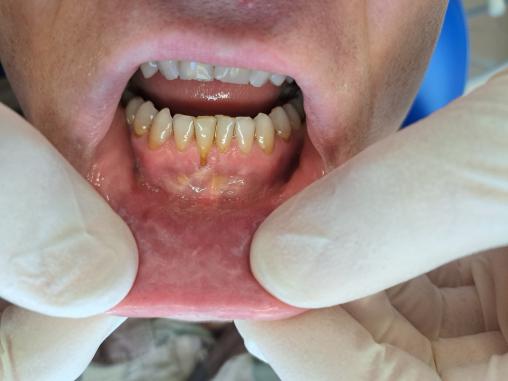

Carlos, militaire de 33 ans, chique du tabac depuis quatre ans environ. Lors d’une consultation, une kératose de la muqueuse de la lèvre inférieure associée à une déhiscence gingivale est observée, à l’endroit même où il place le tabac.

Cliniquement, la leucoplasie de la muqueuse correspond à une plaque kératosique légèrement blanche. Elle ne disparaît pas au grattage ; elle est non indurée, non érythémateuse et indolore. S’y associent parfois des colorations brunâtres liées à la nicotine au niveau de la zone lésée. La découverte de ces lésions est souvent fortuite lors d’une consultation dentaire.